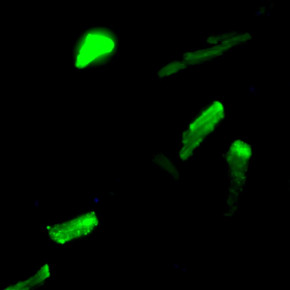

Ученые НИИ кардиологии Томского НИМЦ продолжают поиск новых молекулярных мишеней для повышения толерантности сердца к ишемии-реперфузии

Одно из перспективных направлений - выявление механизмов формирования устойчивости миокарда к ишемическим и реперфузионным повреждениям сердца, возникающей в результате адаптирующих воздействий